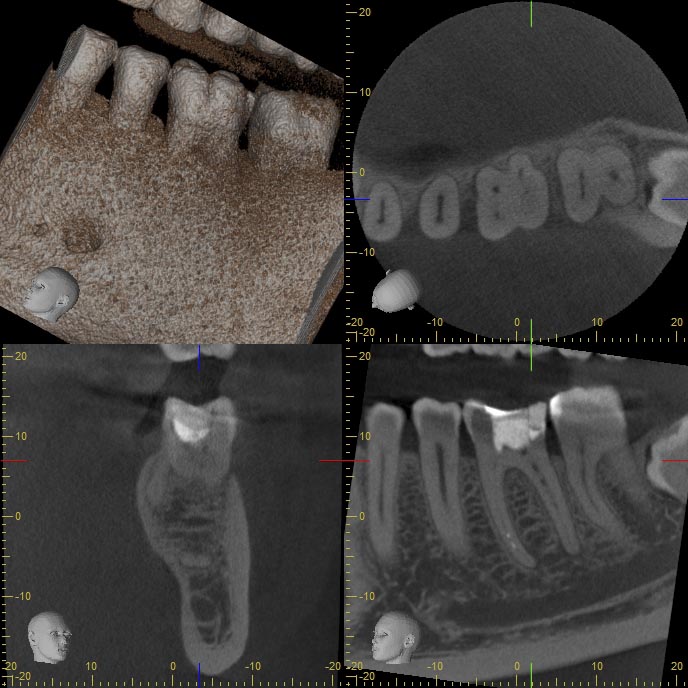

BF36-2 Veröffentlicht 24. Februar 2014 am 688 × 688 in Wann ist ein DVT sinnvoll ? – Fortsetzung Beitrag 13.12.2013